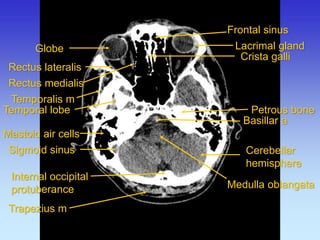

Frontal sinus

Lacrimal gland

Mastoid air cells

Medulla oblangata

Petrous bone

Rectus lateralis

Crista galli

Temporalis m

Temporal lobe

Cerebellar hemisphere

Trapezius m

Sigmoid sinus

Rectus medialis

Globe

Basillar a

Internal occipital protuberance